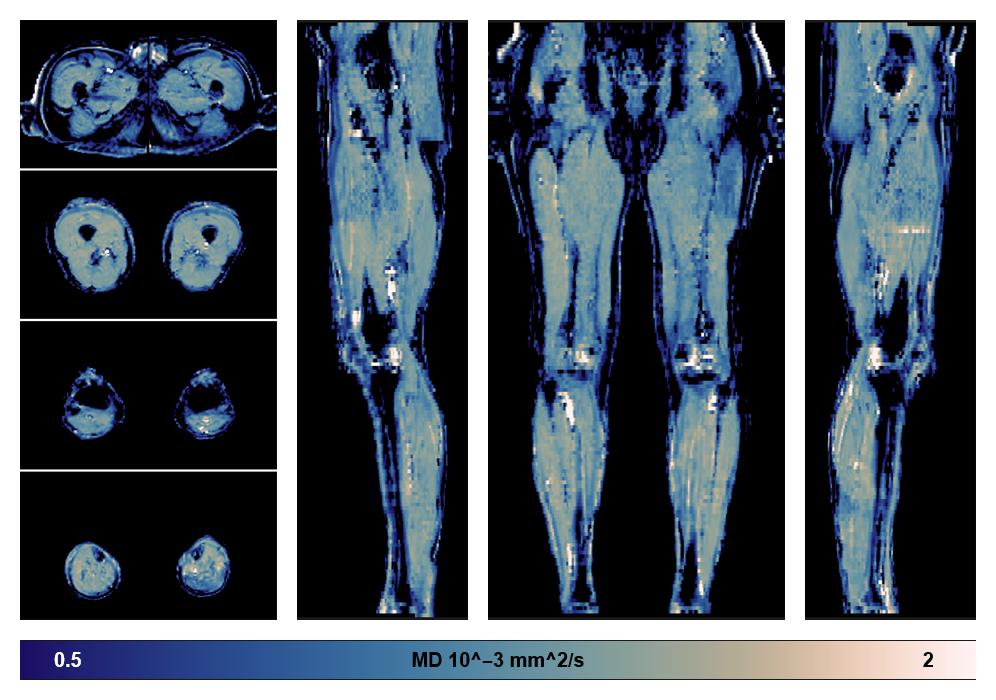

• Mean diffusivity

IVIM corrected whole leg muscle mean diffusivity obtained from diffusion tensor imaging.